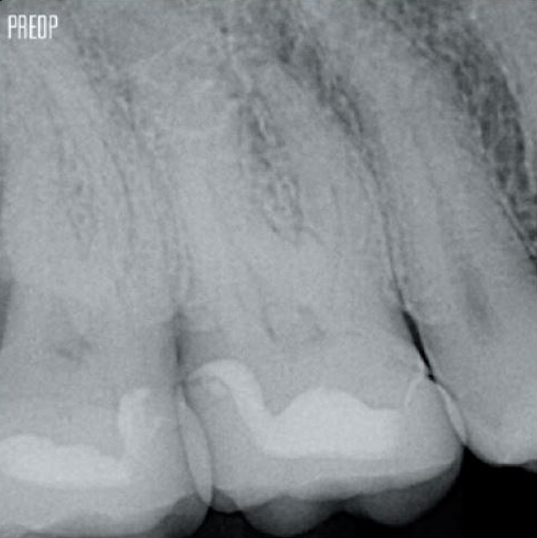

Fotos cortesía del Dr. Ahmed Salman

Más conservación de dentina. Se garantiza la conformación, irrigación y obturación adecuadas.

La conservación de la dentina sirve como base crítica para una restauración de calidad después del tratamiento de conducto radicular. Cuanta más dentina se conserve durante un tratamiento endodóntico, más opciones habrá para realizar una restauración exitosa y duradera.1

Un tratamiento exitoso de conducto radicular comienza con un acceso adecuado a la cámara pulpar. El procedimiento ideal proporciona acceso a la entrada del conducto radicular con una pérdida mínima de dentina.